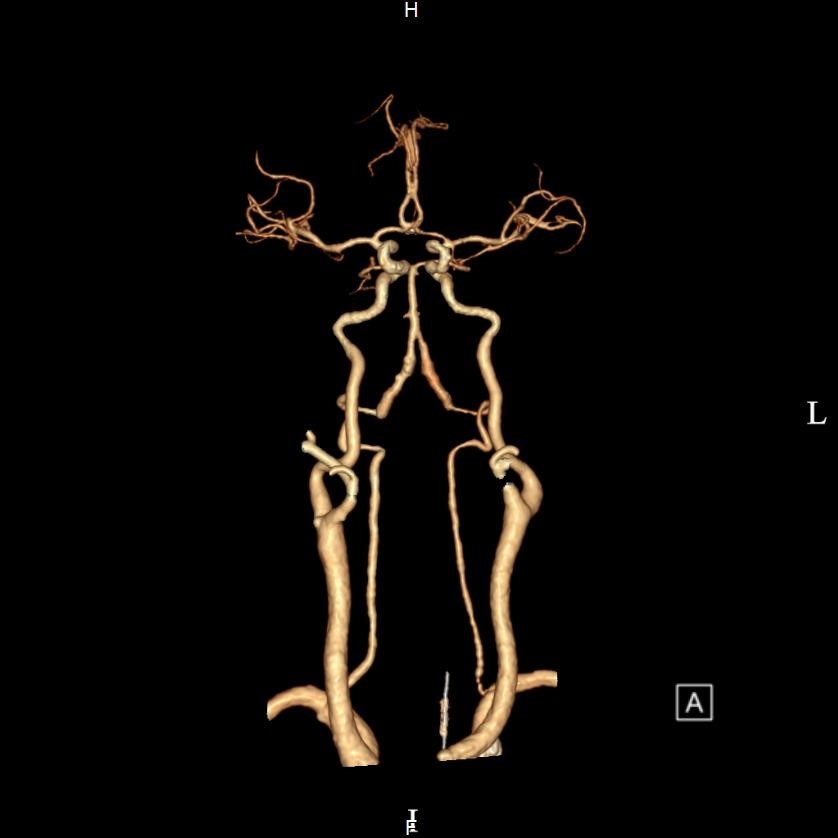

图3:术后复查右侧颈总动脉重新开通,脑部供血良好

术后患者并未立即苏醒,监护室杜隽铭、殷娜主任团队迅速评估,复查血管造影显示脑部血供已恢复通畅,无大面积脑梗死。在张海波护士长带领的护理团队精心照护下,患者历经数日康复,逐渐从昏迷中清醒,肢体活动能力逐步恢复,从微动到自如,最终能够完成指令、开口发声。如今,患者已康复出院,与医护人员结下深厚情谊。